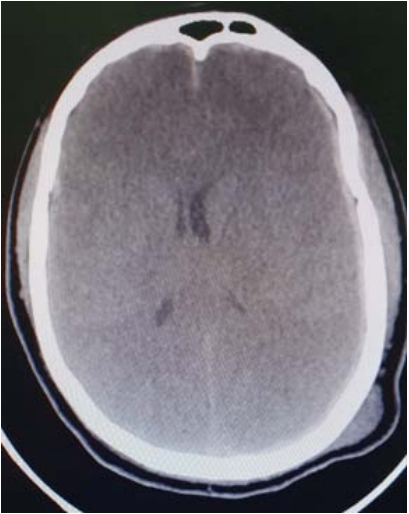

Um paciente de 31 anos de idade, com 90 kg, previamente hígido, foi trazido pelo Serviço de Atendimento Móvel de Urgência (SAMU), em imobilização padrão, após capotamento de automóvel. Relato de Glasgow 12 no momento da cena. AC = RC2T com BNF e FC = 112 bpm, AP = MVF sem RA e FR = 19 irpm, PA = 150 mmHg x 97 mmHg e SatO2 = 96%. Na avaliação inicial, apresenta abertura ocular ao estímulo doloroso com duração inferior a 10 segundos, localizando o estímulo doloroso e sons incompreensíveis, pupilas isocóricas e foto reagentes. A TC de crânio está reproduzida a seguir.

Fonte: Acervo pessoal.

Considerando esse caso clínico e com base nos conhecimentos médicos correlatos, julgue os itens a seguir.

A lesão primária, nesse caso, está associada a maior morbimortalidade quando comparado com hematomas epidurais

A hiperventilação profilática com PaCO2 < 25 mmHg está contraindicada para esse paciente após ser realizada a craniotomia descompressiva.

Para esse paciente estão indicados internação neurocirúrgica, cuidados neurocríticos e craniotomia descompressiva à esquerda por causa do sangramento arterial em tomografia.

O paciente se encontra em Glasgow 9 e apresenta hematoma subdural agudo com desvio de linha média.